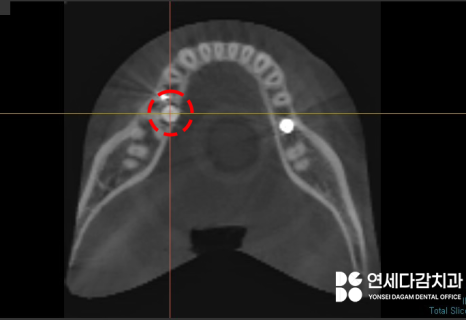

연세다감치과 에서 수술 전

촬영한 CT사진입니다.

2차원 파노라마 뿐만 아니라

3차원 CT를 통해

매복된 정도와 위치를 정확하게 파악한 뒤,

주변 구조물이 손상되지 않도록

조심스럽게 뽑는 것이 중요합니다.

올라오지 못한 채로

설측으로 묻혀있었는데,

여기서 문제는

혀의 감각을 담당하는 설신경(lingual nerve)과

제법 가까운 위치라는 것이었습니다.